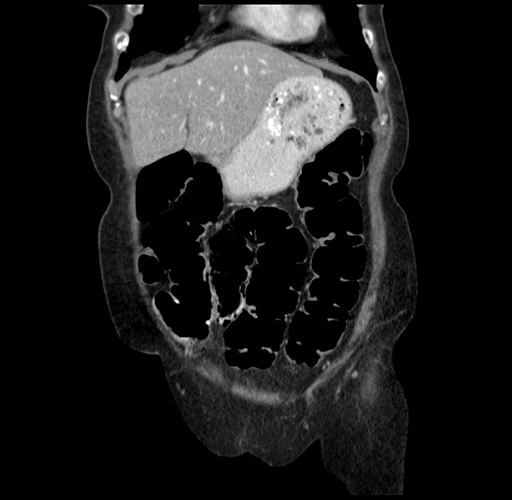

Pre-Chemo: Axial Venous

Axial Venous